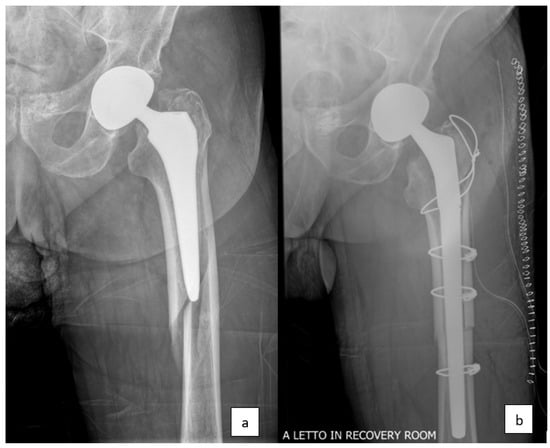

Figure 2.

(a) Periprosthetic femur fracture around the left hip, type Vancouver B2. (b) Revision stem arthroplasty.